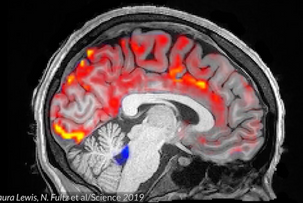

Deep Sleep Triggers Waves of Fluid to Flush Toxins From Brain During Slumber

Everyone knows that a good night’s sleep is vital to physical and psychological health, but understanding exactly what is happening in...